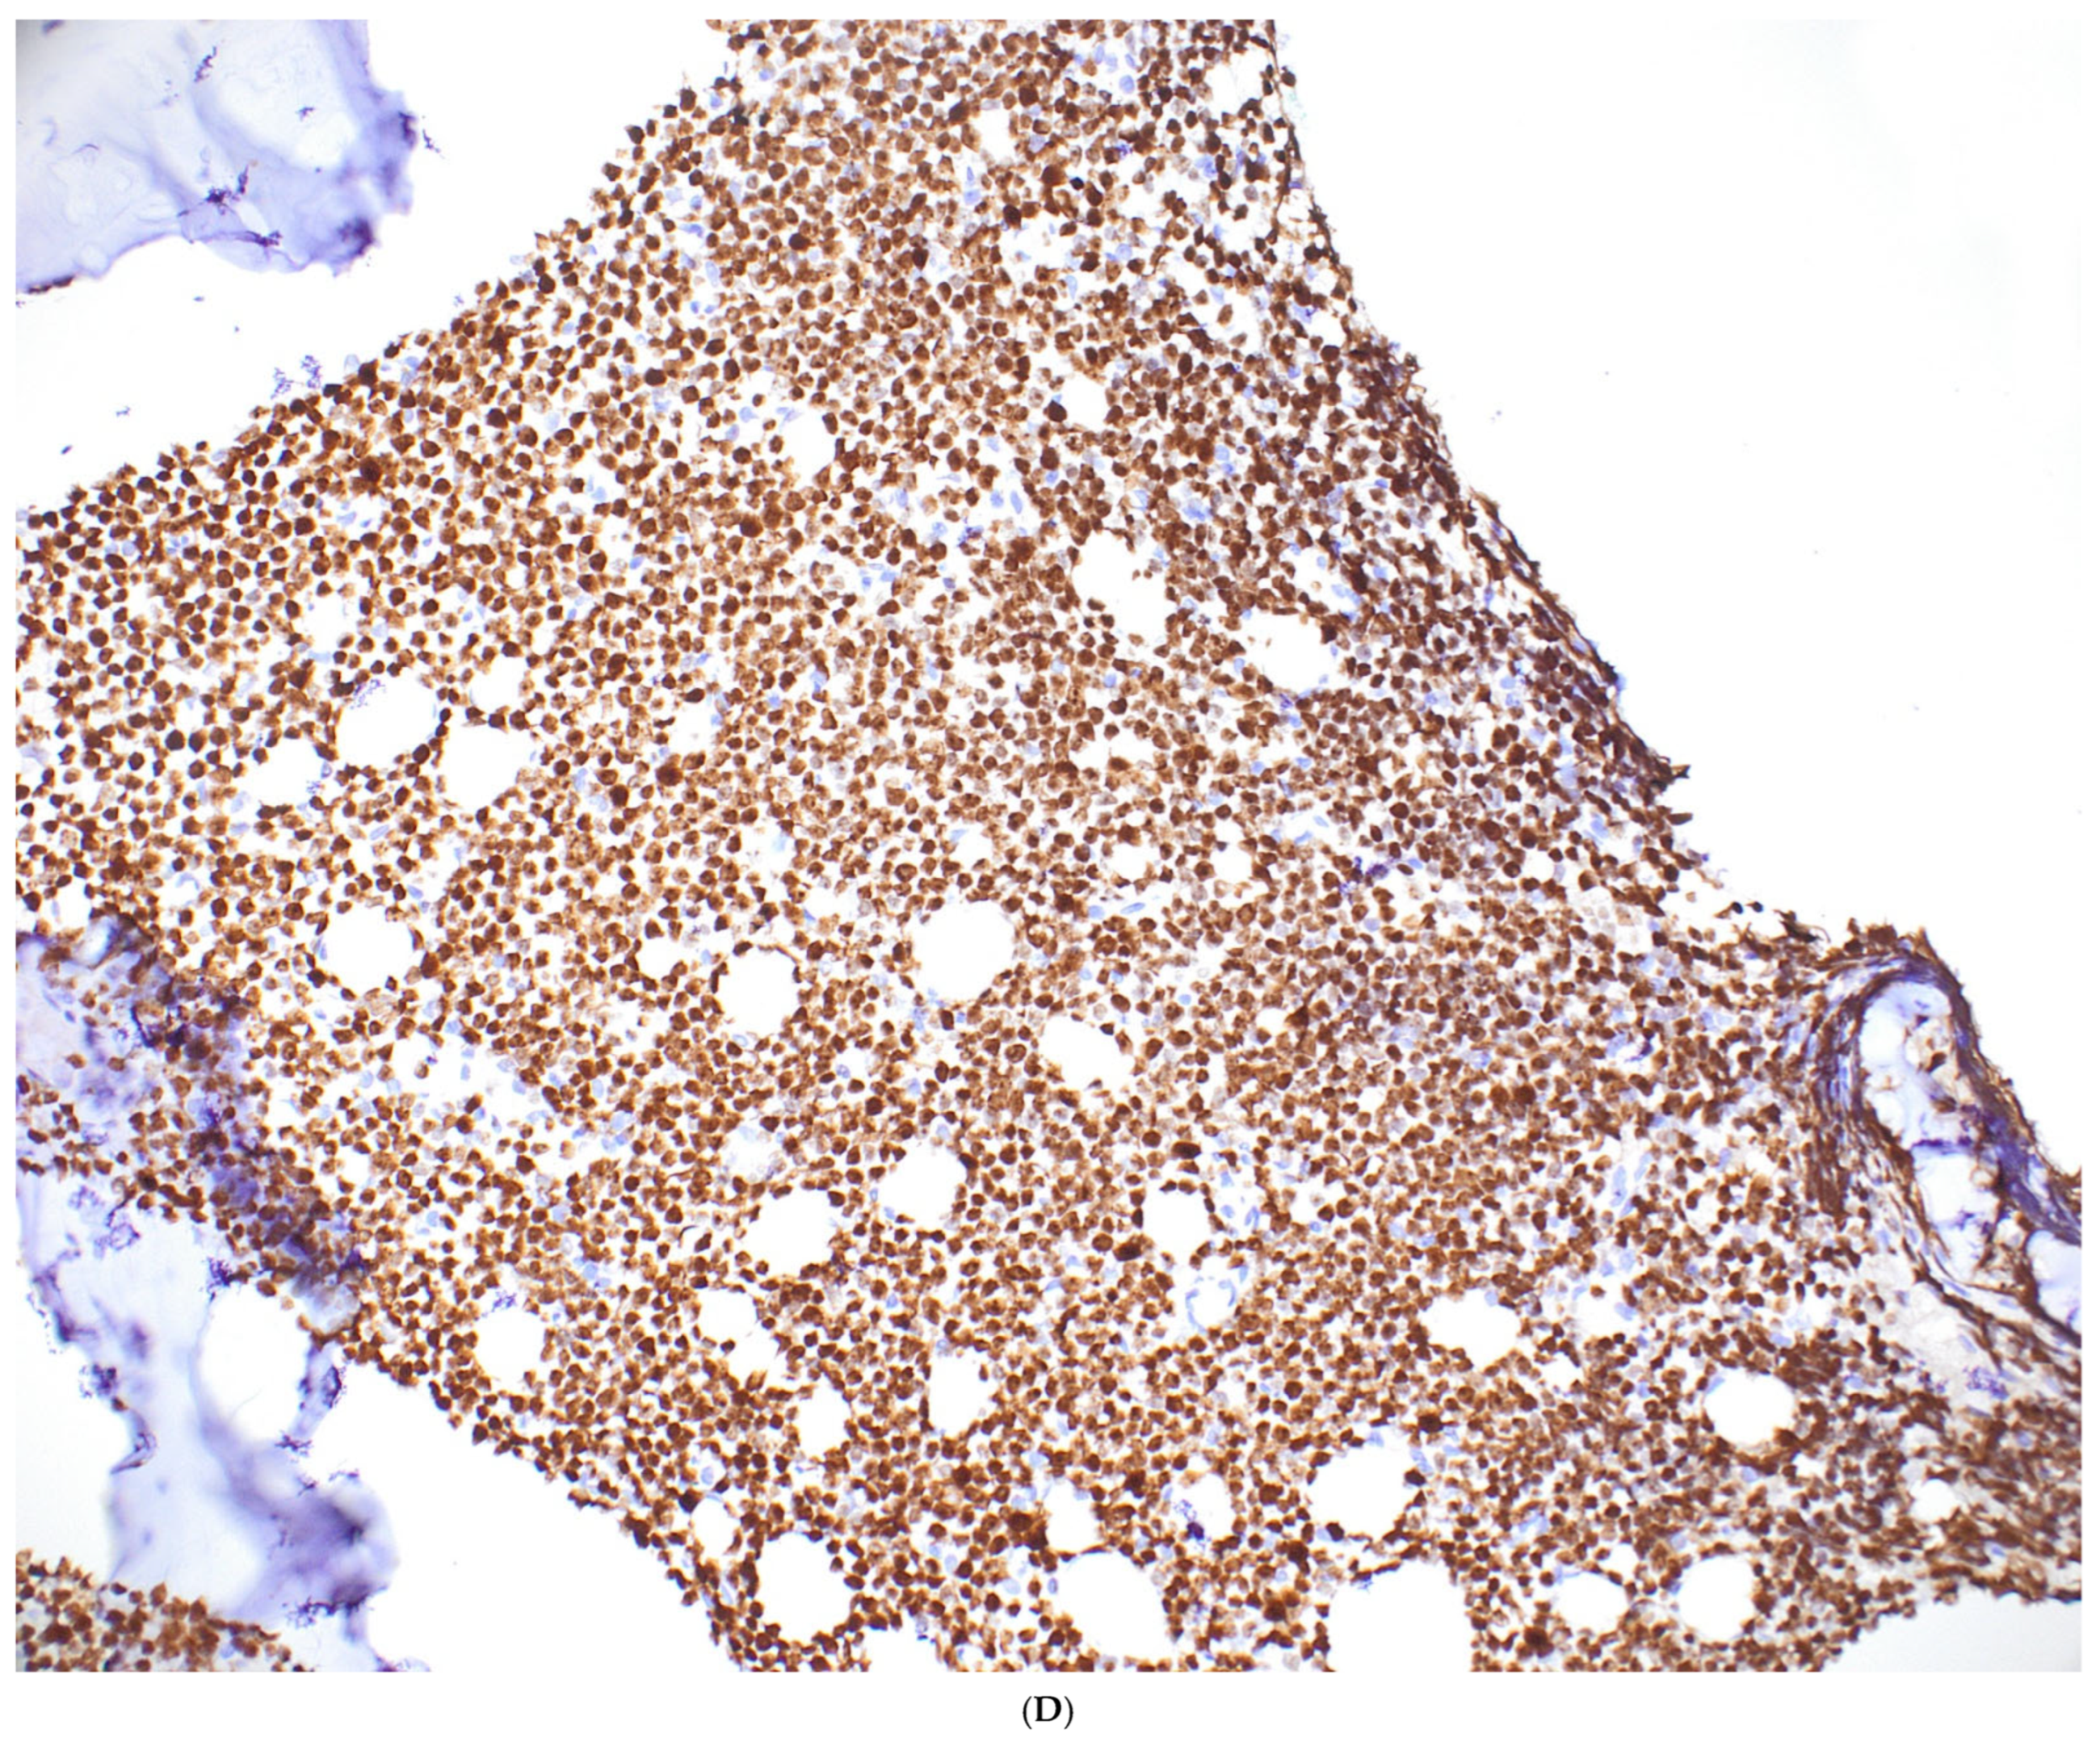

- Expression of CD20 and CD10; absence or weak expression of BCL2; Ki67 index > 95%

- Usually strong expression of MYC (in >80% of cells) and/or demonstration of MYC breakage or IG::MYC translocation

- Starry sky pattern, cohesive growth pattern

- Expression of BCL6 and of CD38, absent expression of terminal deoxynucleotidyl transferase (TdT)